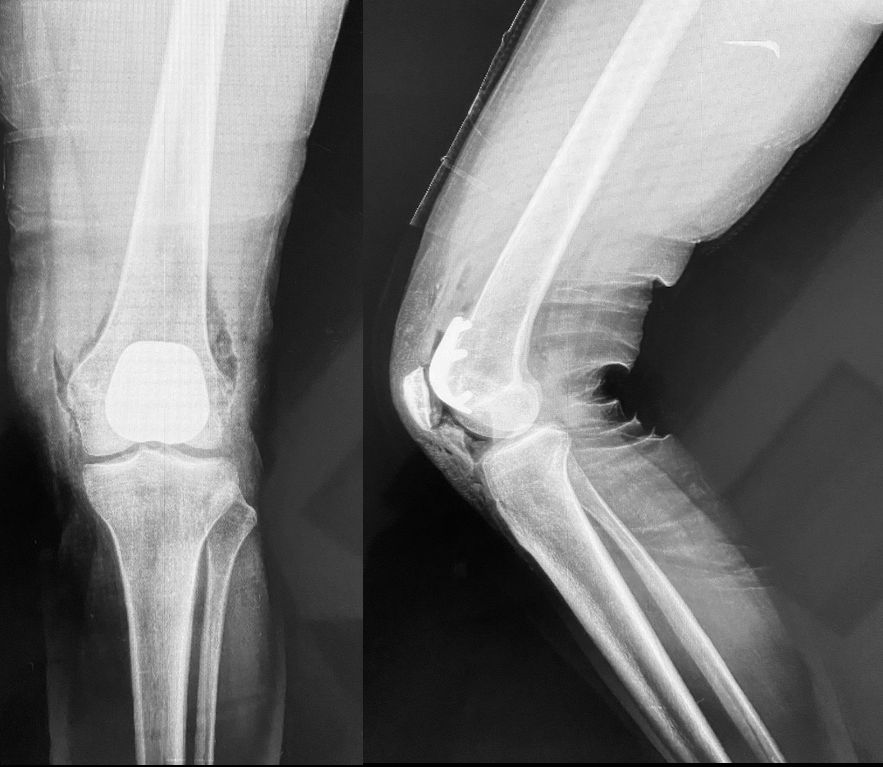

• Artrosis de rodilla

• Osteoartritis

• Deformidades en rodilla